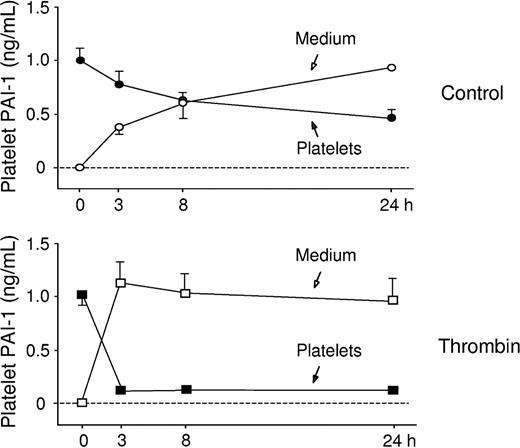

During control conditions, there was a continuous release of PAI-1 from the platelets (P < .0001), and after 24 hours of incubation 67% of platelet PAI-1 was found in the medium.

Thrombin was added to investigate if the synthesis or release rate could be stimulated by a platelet agonist. Platelets were incubated for 1, 3, and 6 hours in the presence of 0.1 U/mL thrombin. As shown in Figure 5, thrombin activation increased the rate of de novo synthesis of PAI-1. Also, the release rate of PAI-1 from the activated platelets was increased, and during thrombin stimulation almost all PAI-1 was released into the medium within the first 3 hours of incubation (Figure 6). Radiolabeling and immunoprecipitation were also performed to study the release of newly synthesized PAI-1 from platelets. Platelet lysate and relisate were studied separately and the results from this assay (data not shown) were in agreement with the findings described. This experiment showed that during thrombin stimulation almost all of the new protein was released into the medium, in contrast to the unstimulated condition where the majority of the radiolabeled PAI-1 was retained within the platelets. When performing radiolabeling studies in the presence of tPA, the PAI-1 synthesized during thrombin stimulation was found to be active.

Analysis of release rate of PAI-1 from activated platelets. To study the release rate of PAI-1, platelets were incubated for 0, 3, 8 and 24 hours and then pelleted and lysed. The PAI-1 concentration in medium and lysate was determined by ELISA. During basal conditions 67% of total PAI-1 was released in 24 hours. As expected, thrombin stimulated the release of PAI-1, and after 3 hours 85% of the total PAI-1 pool was found in the medium (mean ± SEM).

Analysis of release rate of PAI-1 from activated platelets. To study the release rate of PAI-1, platelets were incubated for 0, 3, 8 and 24 hours and then pelleted and lysed. The PAI-1 concentration in medium and lysate was determined by ELISA. During basal conditions 67% of total PAI-1 was released in 24 hours. As expected, thrombin stimulated the release of PAI-1, and after 3 hours 85% of the total PAI-1 pool was found in the medium (mean ± SEM).

In the present study, we demonstrate for the first time that human platelets contain translationally active mRNA for PAI-1 and that there is a continuous de novo synthesis of PAI-1. Substantial amounts of PAI-1 mRNA were detected by real-time PCR and incorporation of radioactive methionine followed by immunoprecipitation confirmed that this mRNA was translated into protein. Over a period of 24 hours, the average total amount of PAI-1 protein in unstimulated platelets increased by 25%. Furthermore, the synthesis rate could be further stimulated when the platelets were activated by thrombin, and thrombin also induced a rapid release of PAI-1 from the activated platelets. Importantly, the newly formed protein was in an active form as shown by its ability to complex-bind and inhibit tPA.

As expected, thrombin stimulated platelet PAI-1 synthesis in a time-dependent manner and also induced a rapid release of PAI-1 from the platelets. Radiolabeling studies in the presence of tPA confirmed that almost all of the PAI-1 synthesized during thrombin stimulation was active. Thus, even if thrombin may also cause release of inactive PAI-1 from the α-granules these observations indicate that thrombin will increase both the absolute and relative amount of active PAI-1 in the relisate. This mechanism may make more active PAI-1 available in a thrombin-rich environment, such as during formation of a blood clot.